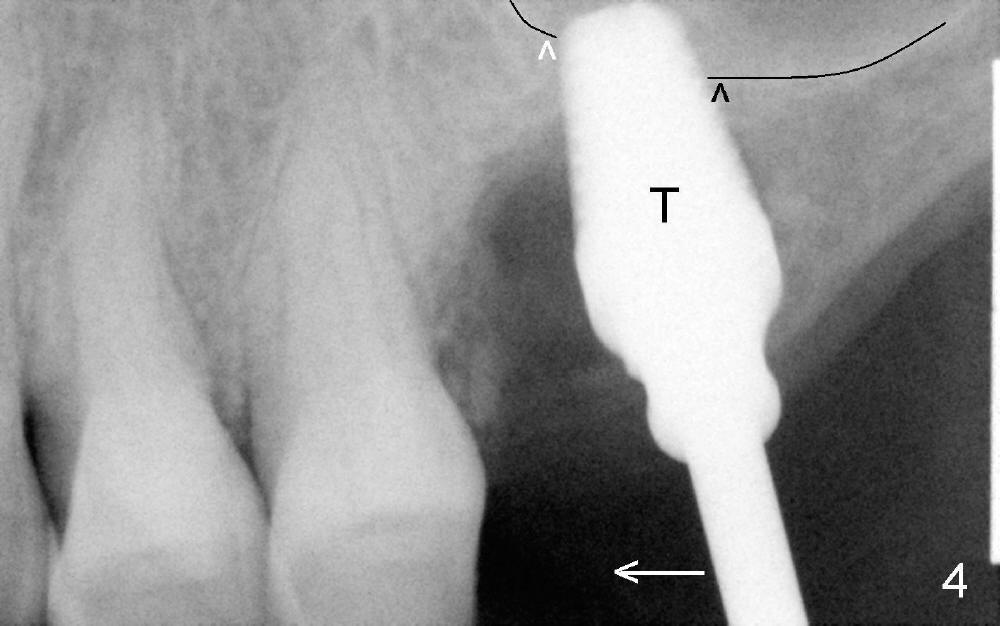

Extraction turns out to be simple with sectioning. After debridment of the socket and soaked with Clindamycin, the ostoeotomy forms using osteotomes, followed by insertion of a tap (Fig.4 T, 6x14 mm). After adjustment of the trajectory (Fig.4 arrow), larger taps are used (7x14, 8x14 mm) before placement of a 8x14 mm implant (Fig.5 I). There is small gap (Fig.6 arrowheads) around the implant. The wound is protected by perio dressing (Fig.7). The dressing is removed 7 days postop. Fig. 8 taken 2 weeks postop shows that the peri-implant gap has closed.